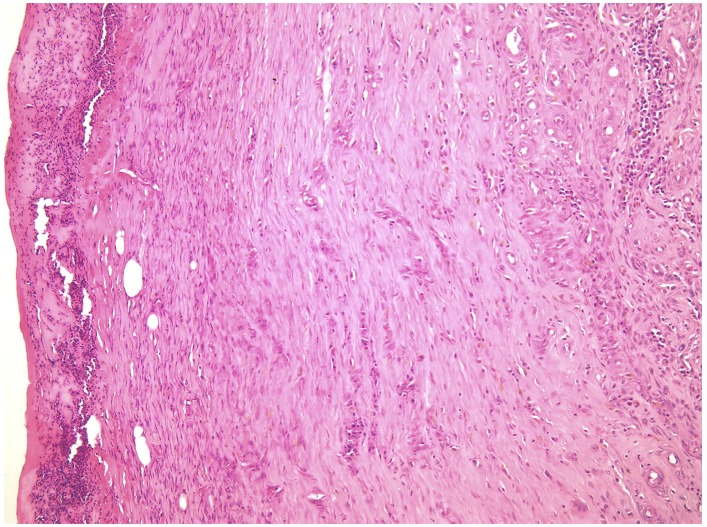

—fibrin clot,

—granulation tissue,

—adipose tissue.